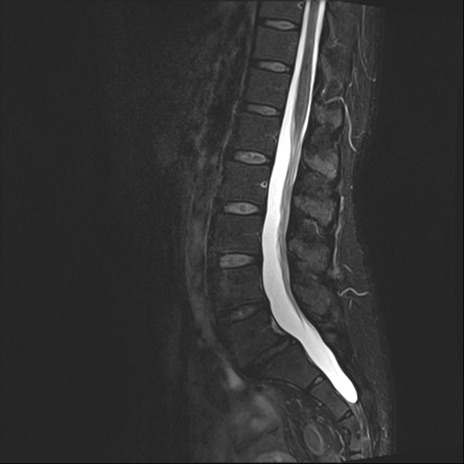

腰椎MRI

T2WI(矢状断像)